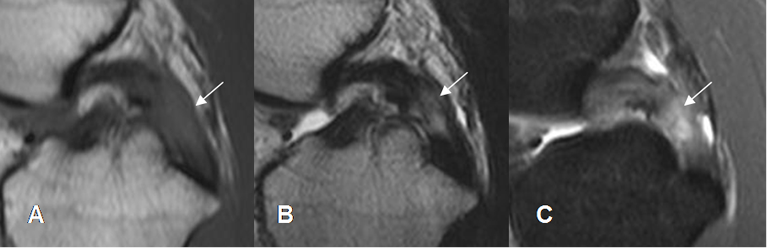

Fig 116. Lesión crónica reagudizada del LCP.

A: RM sagital en T1, B: RM sagital en T2 y C: RM coronal en STIR. Engrosamiento del LCP, por fibrosis reparativa. Existe zona hiperintensa en T2 y STIR, por reagudización.